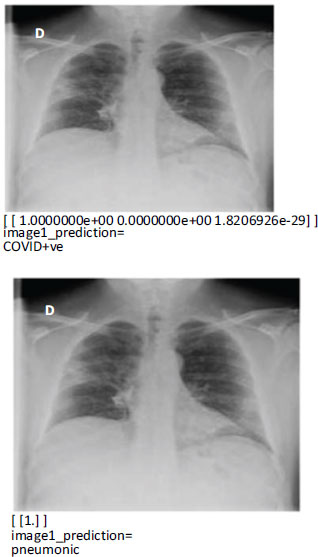

5.4. Model Prediction

Our study is significant because we used only the first chest X-ray data of COVID-19 participants to create a model that predicts early mortality. The predicted images for COVID +ve and Pneumonic diseases are shown in Fig. (9). Early forecasting of patients' clinical outcomes is beneficial for both bed management and treatment. Furthermore, for individuals with severe COVID-19 who are challenging to transfer advanced testing like computed tomography, chest X-rays and laboratory tests are easily accessible. Only using the routinely acquired chest X-ray data from patients with severe COVID-19, we created a deep learning model. We verified the performance enhancement of the ensemble model made possible by combining deep learning models using data from multiple sources, such as X-rays of the chest and electronic health records.